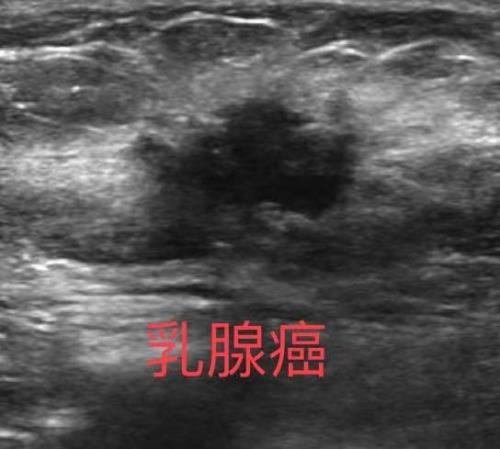

乳腺彩超检查是利用超声仪器将超声波发射到乳腺获得声像图,根据声像图显示的病灶的大小、形态、轮廓边界、回声类型、回声内部情况及后方衰减情况等判断病变的性质。

在乳腺自我检査或体检触摸到乳腺肿块时。2、发现乳头有溢液,尤其是血性时或乳头内陷以及局部皮肤的改变。3、无症状的乳腺癌的高危人群,可以定期做乳腺的超声检查。4、发现乳腺肿块时,鉴別肿块的性质,如肿块是囊性,囊实性或者是良恶性的鉴别。5、乳腺出现炎性表现时,用于鉴别急性乳腺炎、乳腺脓肿和炎性乳腺癌。6、乳腺良性病变的随访以及乳腺癌术后的随访。7、美容隆胸后及其并发症的监测。 8、具有乳腺高危人群,包括:初潮年龄早、绝经年龄晚、晚婚、晚育、未生育、未哺乳、乳腺癌家族性遗传史、有烟酒嗜好的女性等。

1、乳腺彩超检查操作简便、安全、无辐射,并可多切面、动态观察及测量肿块血流,对受检者无痛苦,无放射性损害,可以短期多次反复进行,适用于任何年龄层女性,包括妊娠期和哺乳期女性。2、乳腺彩超检査能较好的显示乳腺肿块的特征,可鉴别在X线片上看不到,但可触及的肿物,也可用于不能行乳腺钼靶检査的女性(如孕妇等)。3、超声对软组织有良好的分辨力,能够清晰的显示乳房及胸壁的各层结构,可以确定病变的解剖部位和层次,鉴别乳腺肿块和胸壁肿块。4、根据声像图表现,结合血流,可以推断肿块的良恶性,并可发现有无局部及远处转移。5、若发现乳房有肿块,还可在超声引导下进行穿刺、活检及治疗。6、随访方便。